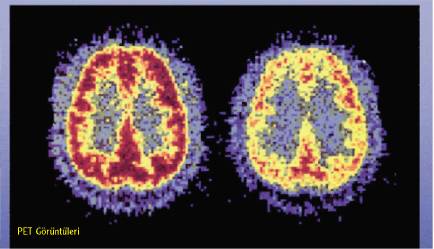

nb-7.jpg

Hayvan deneyleri

nb-8.jpg nb-9.jpg

sine ait almaç sayısı azaldığından, do­pamin üretici sistemi yeterince uyara-mazlar. Bu durumda kişi hiçbir şey­den zevk alamaz ve depresyona girer. Kokaine bağlı yoksunluk sendromu, depresyon şeklinde ortaya çıkar. Kişi, bu sefer depresyondan sakınmak için kokain kullanmaya devam eder. (Bilim-insanlarının, kokainin beyin fonksi­yonları üzerindeki etkisini görmek için pozitron emisyon tomografisi -PET görüntüleme yöntemiyle yaptık­ları çalışmalar, kokain alımıyla beyin metabolik etkinliğinin azaldığını gös­termiş bulunuyor.)